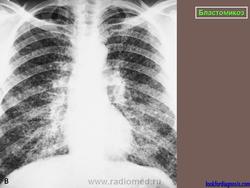

Рентгенологически отмечаются выраженные изменения лимфатических узлов средостения, очаговые инфильтраты, в некоторых из них развиваются каверны с неправильными контурами. При диссеминации процесс захватывает многие органы, эти формы часто заканчиваются гибелью больного.